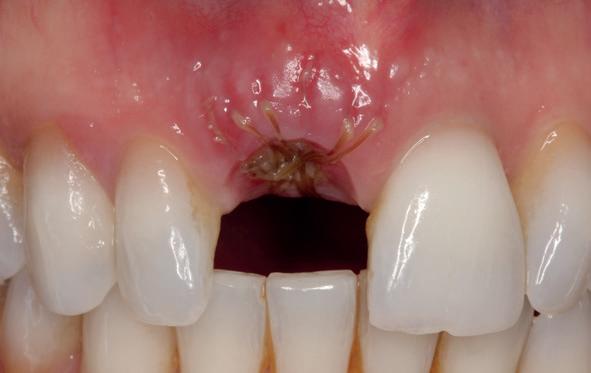

Implantologische behandelingen in het esthetische front vragen meer dan technische vaardigheid alleen. Ze vragen om overzicht, timing, vertrouwen en een team dat als vanzelf samenwerkt onder druk. Juist bij complexe casussen, waarin angst, infectie en hoge esthetische verwachtingen samenkomen, wordt zichtbaar hoe bepalend de rol van de tandartsassistent is.

Deze casus beschrijft een uitgebreide immediate implantaatbehandeling bij een patiënt die door meerdere collega’s werd geweigerd. Niet omdat de mogelijkheden ontbraken, maar omdat de complexiteit vroeg om een perfect afgestemde samenwerking. Het verhaal laat zien hoe de assistent in zo’n traject veel meer is dan een uitvoerende kracht of “mal”, maar een dynamische surgical guide die het proces mede stuurt, bewaakt en mogelijk maakt.De patiënt: wanneer alles samenkomt

Na het klinische onderzoek volgde het röntgenologisch traject. De CBCT liet precies zien wat we al vreesden: een front waarin het bot onregelmatig was, duidelijke radiolucenties rond de pijlers en een infectiegebied dat zich onder vrijwel de gehele brug had verspreid. Tegelijkertijd was er ook potentie. Net voldoende botstructuur om immediate implantaatplaatsing te overwegen, mits alles perfect gepland zou worden.